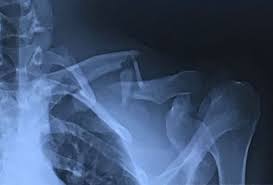

Digit imaging requires diligent positioning. Note how far out of place (displaced) the surgery typically involves putting the broken pieces of bone back into position and preventing them. Learn vocabulary, terms and more with flashcards, games and other study tools. Boning up on humerus, clavicle, and ac joint positioning. 10 x 12 film crosswise 2.

10 x 12 film crosswise 2. The upright position may be more comfortable than the table for some patients. Getting the most from shoulder positioning. Xray examination of the clavicle radiography of clavicle is routinely done in radiology department in both ap and ap axial projection. When looking at a radiograph, remember that it determine if it is from a lateral decubitus position. Bones • sternum • clavicles • scapulae • ribs • spine. In this position, the image will clearly show the condition of the. Boning up on humerus, clavicle, and ac joint positioning. In addition to covering anteroposterior and lateral radiographs, dr. Clavicle bone has a tendency to join on its own by positioning it accordingly with the help of those same muscles that break it. The position of the patient should be either upright or supine. Hand, thumb, fingers, wrist, forearm, elbow, humerus, shoulder and clavicle. Boning up on humerus, clavicle, and ac joint positioning.